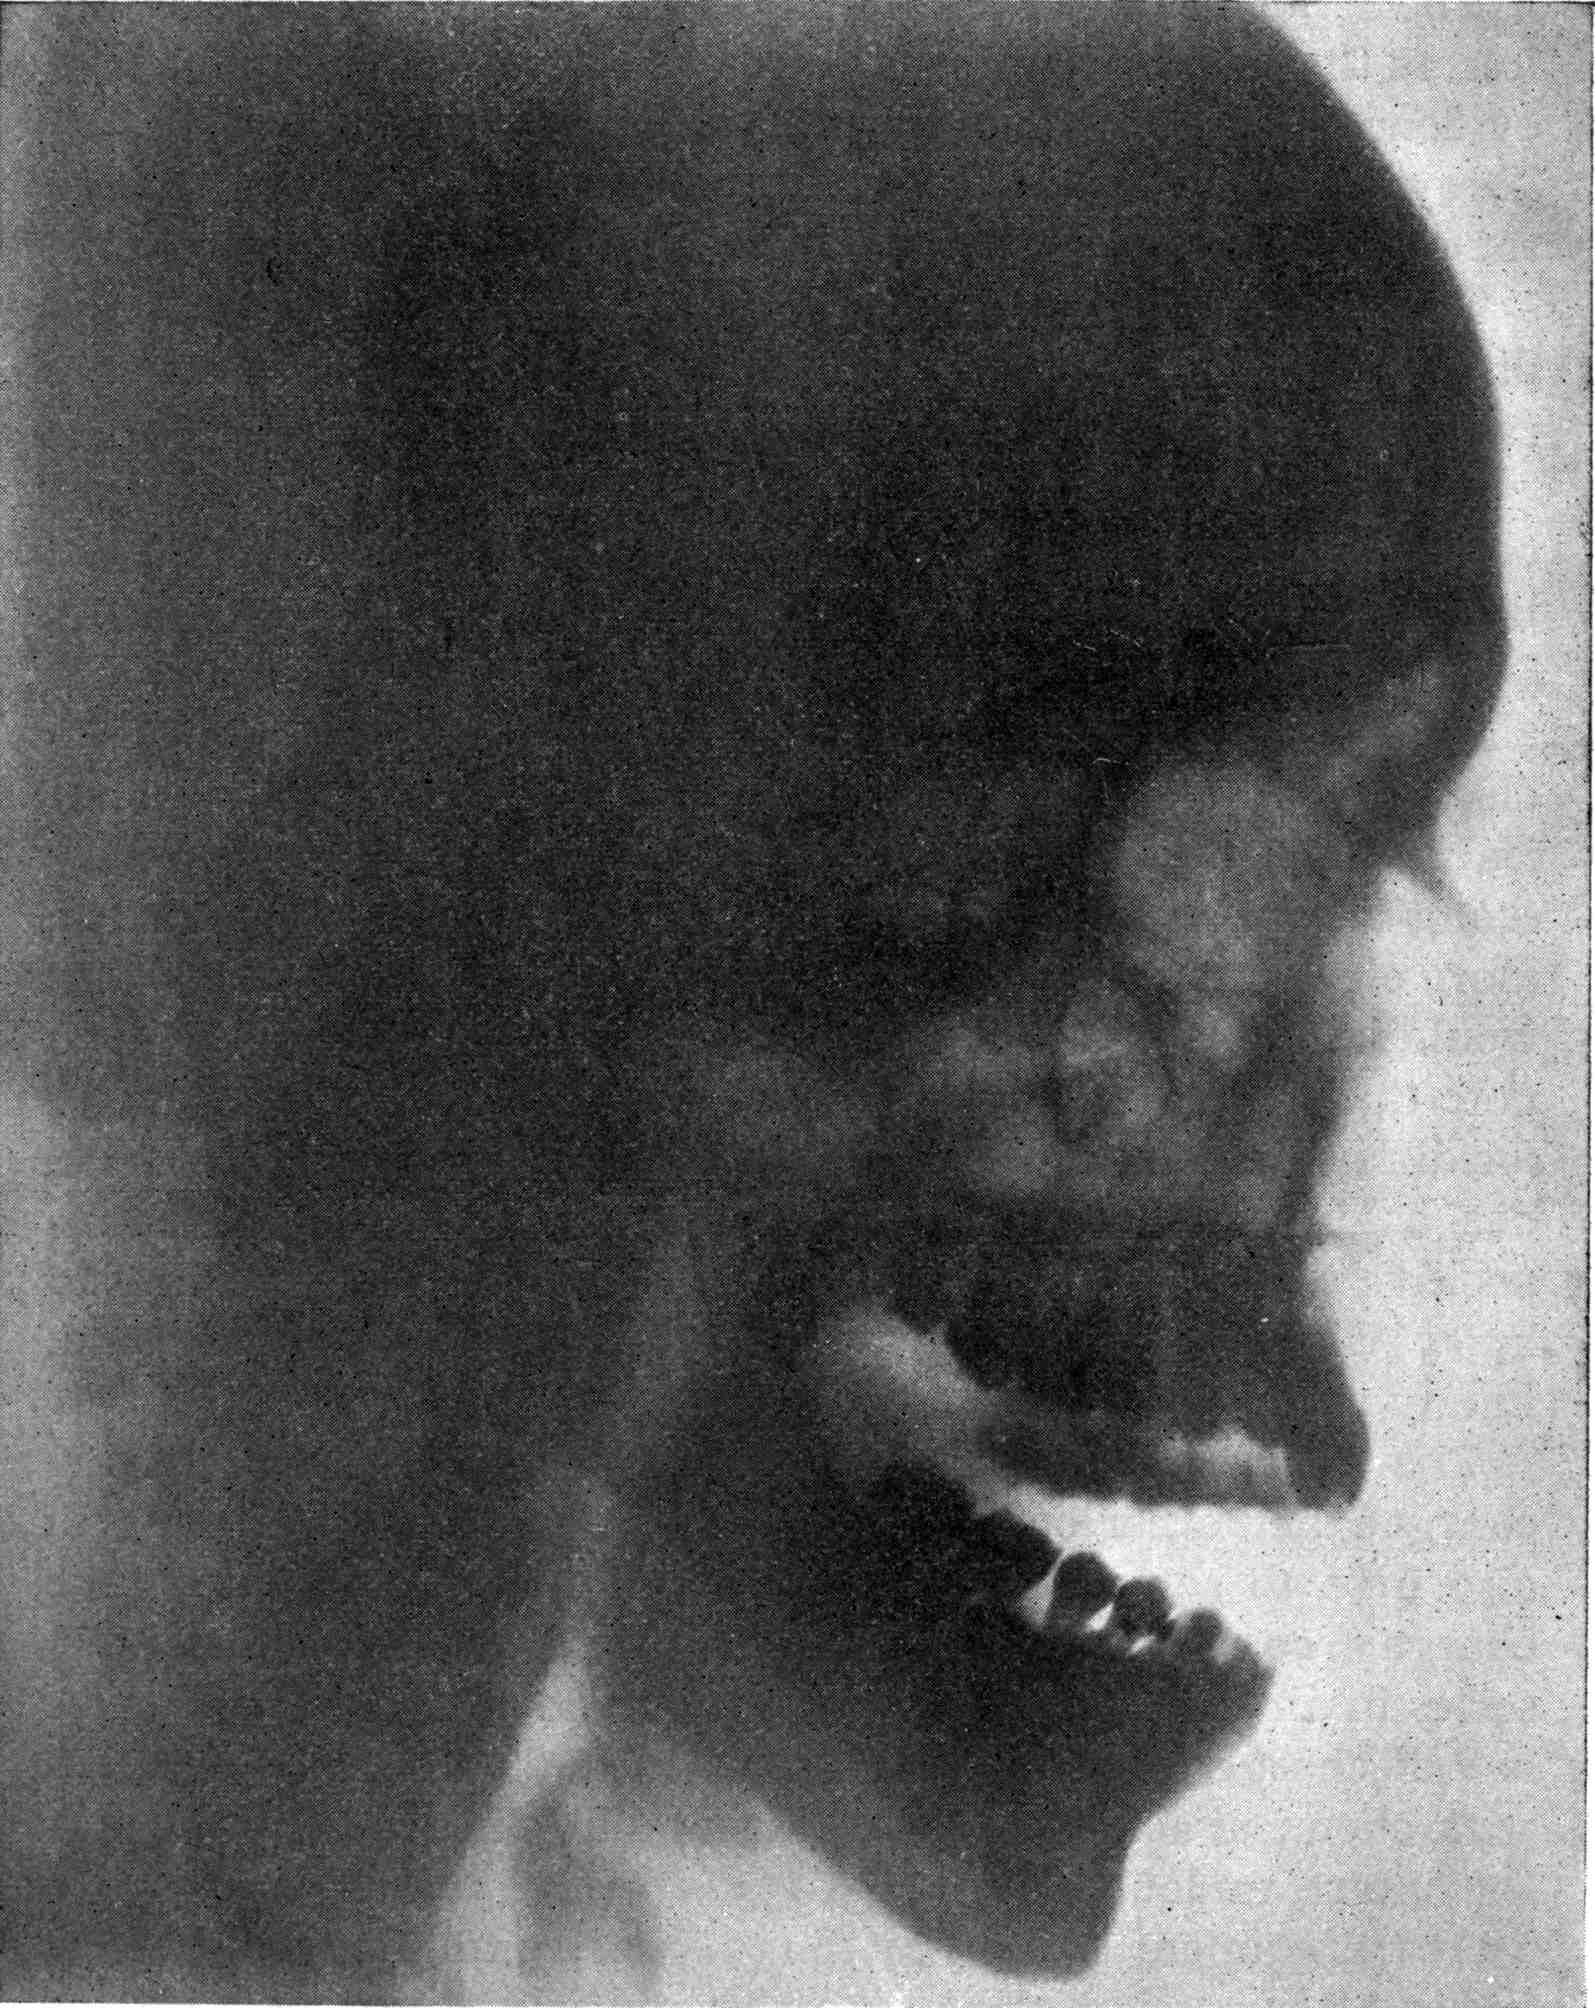

Fig. 1.—Head.